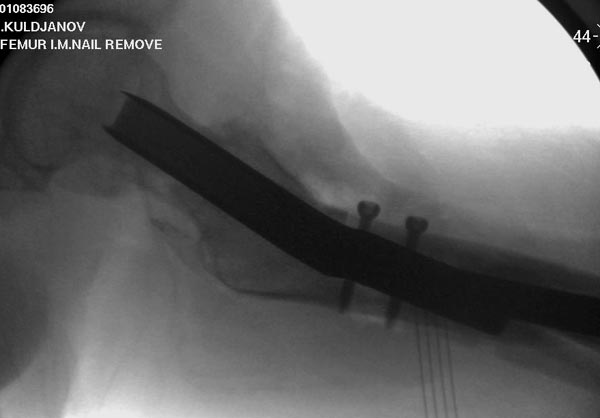

Здесь выставлен ренгенограммы больного, ему 21, травму получил в результате высокоскоростной погони на украденной машине, которая закончилась смертью трех остальных “боевых комрадов”. Начатую коллегой открытую операцию на шейке пришлось закончить мне, установкой винтов и ретроградной фиксацией бедра. Выписка в обычное сроки и наблюдался амбулаторно. Каждый раз напоминали о возможности осложнений ввиде несращения! По истечению 4 месяцев появились признаки варусной деформации. На СТ срезах несращение шейки и бедра. Риминг, замена на более толстый гвоздь и вальгусная остеотомия.

Сразу скажу, что пациент вчера (8.04) прооперирован - артротомия, остеосинтез мыщелков большеберцовой кости канюлированными винтами, открытая репозиция отломков бедренной кости, ретроградный БИОС, остеосинтез надколенника (центральных его отломков) спицами с проволочной петлей. Двухкратная попытка закрытой репозиции шейки на операционном столе после синтеза бедра - абсолютно неэффективна. Учитывая продолжительность и травматичность операции, шейка отложена на 2-й этап. Плечо наверное на 3-й (если вообще делать). Снимки постараюсь предоставить, но чуть позже.